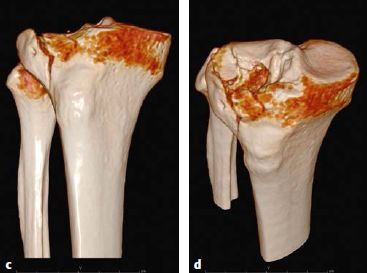

图6.8.1-20 a-d

a  CT冠状位图像显示外侧平台的劈裂-塌陷骨折;b  CT横断位显示外侧平台前外侧关节面的严重缺失;c-d  三维CT图像